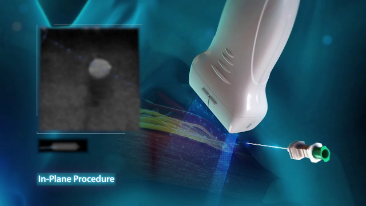

Mindray? ??? ??? ?? ??? ???? ??? ?? ??? ??? ????? ??? ????. ?? ???? ZONE Sonography? ??? ???? ?? Resona 7? ??? ZST+ ???? ?? ?? ? ?? ??? ????? ?? ??? ??? ??? ? ?? ????.

?? Resona 7? ???? ??? ?? ???? ??? ??? ???? ??? ?? ???? V Flow? ?? CNS ??? ?? 3D ??? ???? ?? ???? ?? ??? ?? ?? ?? ??? ??????. ???? ??? ??? ?? ?? ??? ??? ?? ?? ??? ??? Resona 7? ??? ???? ???? ??? ??? ??? ????.